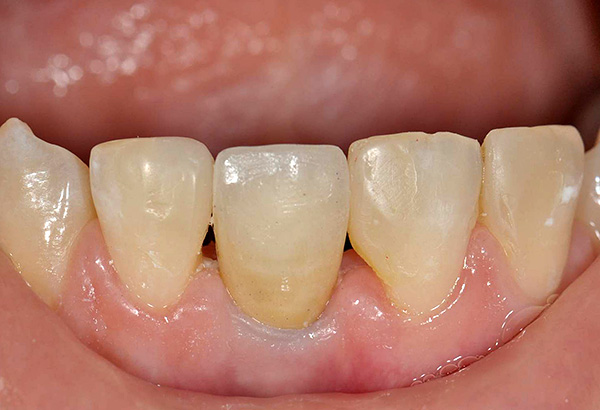

- Trattamento dentale e gengivale, rimozione di placca e tartaro, che aiuta a ripristinare il colore naturale dello smalto - questo è necessario per la selezione esatta del colore delle corone dentali;

Le fotografie seguenti mostrano un esempio corrispondente (posizionamento di un impianto al posto di un dente estratto dopo la guarigione di un foro):